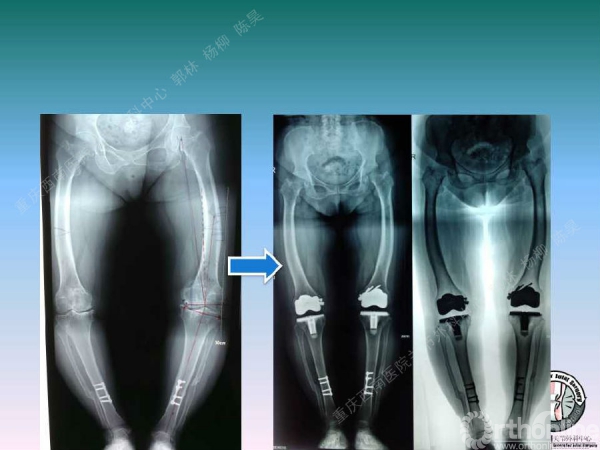

导读:文中,来自重庆西南医院的郭林教授为大家介绍了股骨冠状位关节外畸形的TKA的相关知识,并详细阐述了关节外畸形的概念、诊断、关节内滑移截骨技术等相关内容。

关节外截骨纠正关节外畸形

滑移截骨纠正关节外畸形